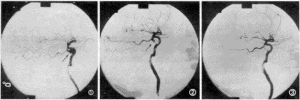

慢性化膿性中耳炎--X光片對骨瘍型慢性化膿性中耳炎的治療也應酌性處理,骨瘍型常伴有中耳腔內芽,由於它堵塞鼓膜穿孔,使膿液難以排除,若容易取出中耳肉芽則應取出,促進膿液流出,如果觸動肉芽會出現眩暈和面肌抽搐,則說明肉芽與耳內的重要機構相關連。凡遇到上述情況不得盲目牽拉肉芽組織,若乳突X線拍片顯示的乳突骨質破壞,則應進行乳突根治手術治療

對膽脂瘤型慢性化膿性中耳炎的治療,則應儘早治療,或早施行乳突根治手術。因為此型極易破壞鼓室和乳突的結構,使半規管和面神經的骨管破壞吸收,以致出現迷路炎和面神經癱瘓;同時也能破壞鼓室與乳突的頂壁,在中耳乳突和顱腦間的骨板形成缺損,乳突後部的乙狀竇骨壁也可因為膽脂瘤壓迫而吸收破壞,極易造成細菌進行顱內,引起化膿性腦膜炎,顱內膿腫等嚴重的顱內併發症。慢性中耳炎併發症多,危害也大,因中耳炎症反覆發作,內耳的細菌也會逐漸變異為去它乾菌而產生抗藥,建議最好是選擇專業性對症治療,而採用中醫藥治療慢性中耳炎,特別是對很多抗生素而產生耐藥的患者.

慢性化膿性中耳炎(二)骨瘍型:乳突X線攝片為硬化型或板障型,伴有骨質缺損破壞。

(三)膽脂瘤型:乳突X線攝片示上鼓室、鼓竇或乳突有骨質破壞區,邊緣多濃密、整齊。

治療原則為消除病因,控制感染,通暢引流,徹底清除病灶,防治併發症;重建聽力。